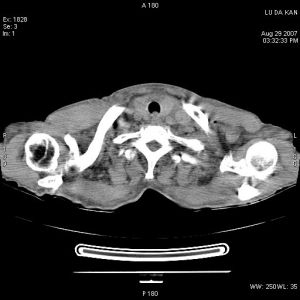

可發現肺部原發病灶、縱隔增寬或肺門淋巴結增大。胸部CT或MRI檢查

有助於明確上腔靜脈阻塞的原因。其他